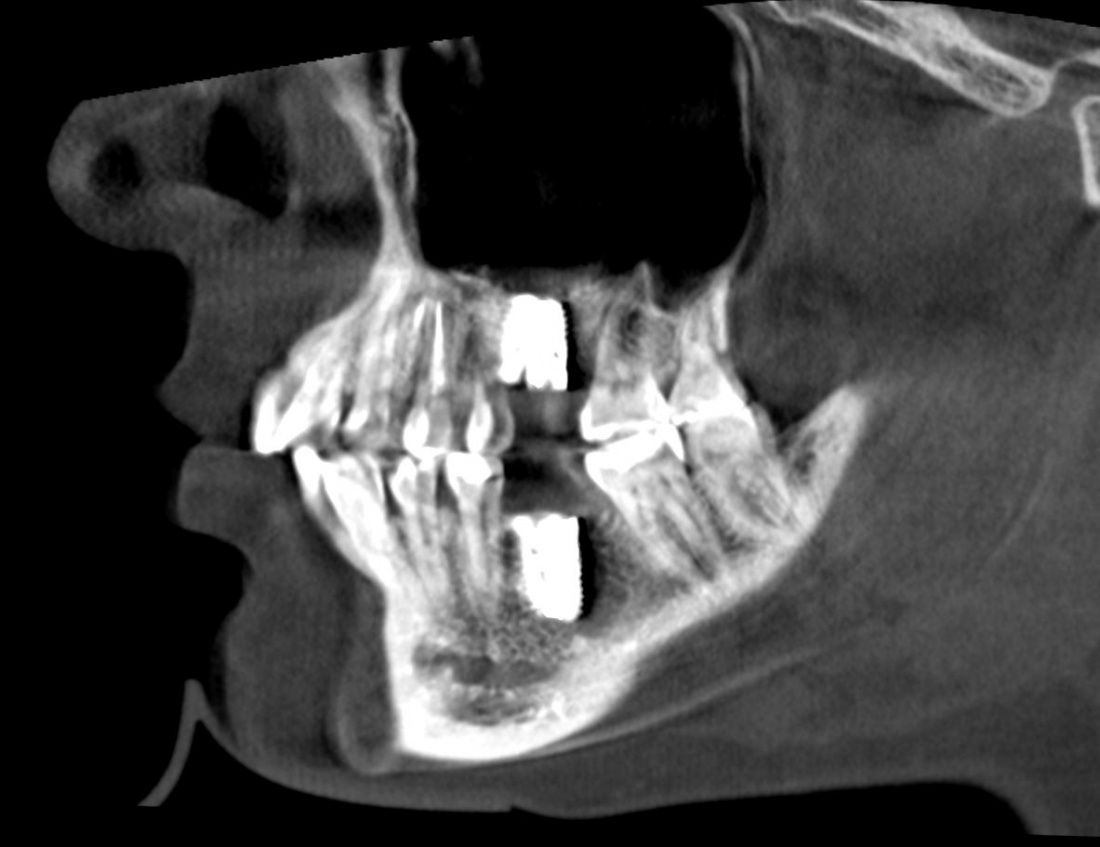

Если сделать КЛКТ на этом этапе (через 2-3 недели после операции), то иногда мы можем увидеть утолщение слизистой оболочки в области дна альвеолярной бухты, вплоть до рентгенологической картины гайморита:

однако, в течение последующего месяца (при соответствующей терапии) рентгенологическая картина возвращается к нормальной: